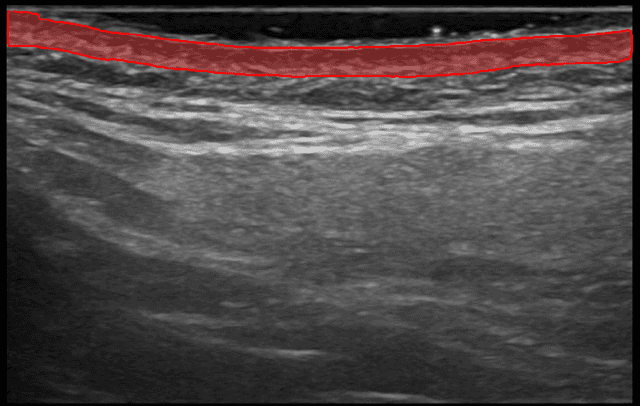

Seguimiento Visual del Progreso

Sigue mejoras medibles a lo largo de las sesiones de tratamiento. Visualiza cambios en la calidad de la dermis con comparaciones precisas de antes y después.